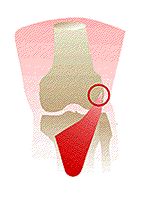

Osteocondrite dissecante (m. di Konig)

Si tratta di una necrosi parcellare che interessa solo una piccola parte, lenticolare, della cartilagine articolare e della corrispondente spongiosa subcondrale dell’epifisi distale del femore o dell’omero.

Il frammento osseo, in preda a fenomeni necrotici, si demarca nettamente dal tessuto osteocartilagìneo circostante fino a distaccarsi e cadere libero. nell’articolazione (“topo” articolare).